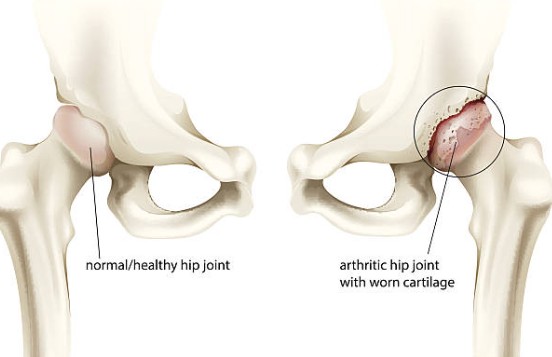

Hip dysplasia is a common skeletal condition, often seen in large or giant breed dogs, although it can occur in smaller breeds, as well. To understand how the condition works, owners first must understand the basic anatomy of the hip joint.

- The hip joint functions as a ball and socket. In dogs with hip dysplasia, the ball and socket do not fit or develop properly. Therefore, they rub and grind instead of sliding smoothly. This results in deterioration over time and an eventual loss of function of the joint itself.

Canine hip dysplasia is a skeletal condition that negatively impacts the anatomy of a dog’s hip joint and hip function over time. You may already know that the hip joint is designed to function like a ball and socket, where the two parts of the joint work in tandem by sliding smoothly together.

- In a healthy hip joint, this cohesive function allows for a wide range of movements to be executed easily and comfortably so that your dog can bound around playing fetch, chasing squirrels, or getting their zoomies out without feeling any pain.

- But when a dog suffers from hip dysplasia, the ball and socket elements that make up their hip joint rub and grind unpleasantly against one another, resulting in hip function deterioration over time.